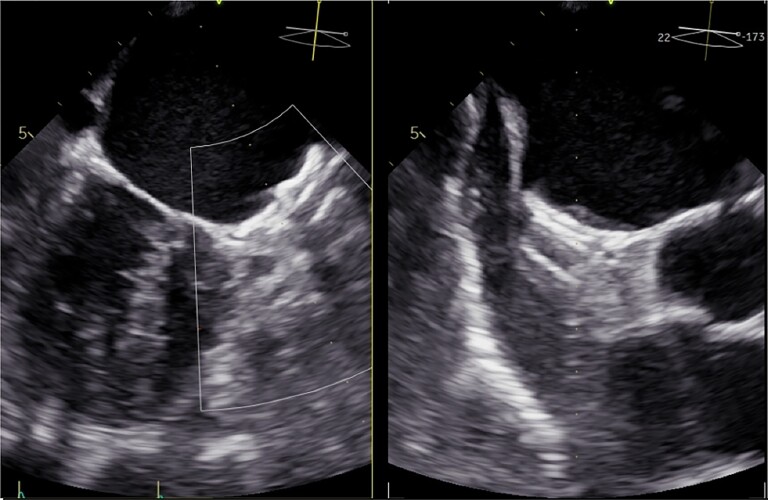

An 83-year-old woman was admitted to the hospital with fever (38.6°), lasting for 2 days, accompanied by chills, fatigue, and decreased alertness. The patient did not take any medication or antibiotics before admission or undergo any invasive procedure with the potential for bacteraemia during the previous year. The patient had a history of arterial hypertension, pulmonary hypertension, severe tricuspid regurgitation, and permanent AF and had received an LAAO (Amplatzer amulet©) 20 months before admission for recurrent bleedings on different oral anticoagulants (vitamin K antagonists and apixaban). The LAAO implantation had been uneventful. The patient had been treated for three months with aspirin and clopidogrel. A routine TEE examination (Figure 1, Supplementary material online, Videos S1–S3) 3 months after implantation had confirmed the correct position of the device without leakage.

Figure 1.

Transesophageal echocardiography 3 months after implantation.